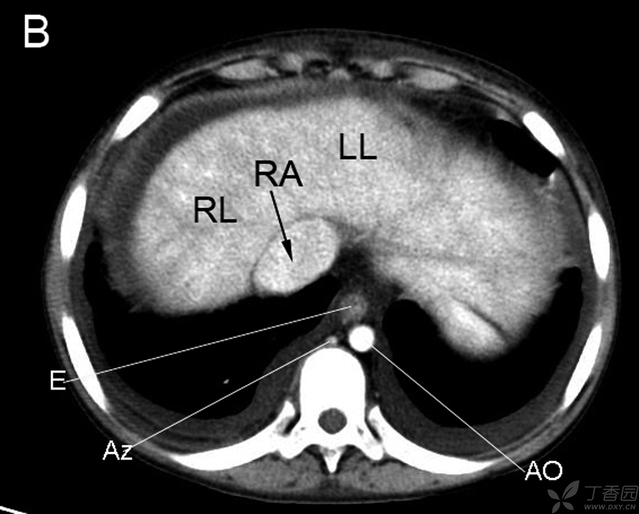

RB右支气管 LA左房 LB左支气管 E食管 AZ奇静脉 AO主动脉

LL左肝 RA右房 RL右肝